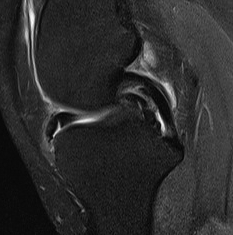

MRI Classification

Stoller 1987 J. Radiol.

Grade 0

- normal homogeneous low signal intensity

Grade I

- globular increase signal in meniscus

- doesn't reach either surface

Grade II

- linear increase signal, doesn't reach surface

- myxoid intra-meniscal degeneration / partially healed tear

Grade III

- increased signal intensity communicates with meniscal surface

- 70-90% accurate for true tear

- accuracy MM > LM